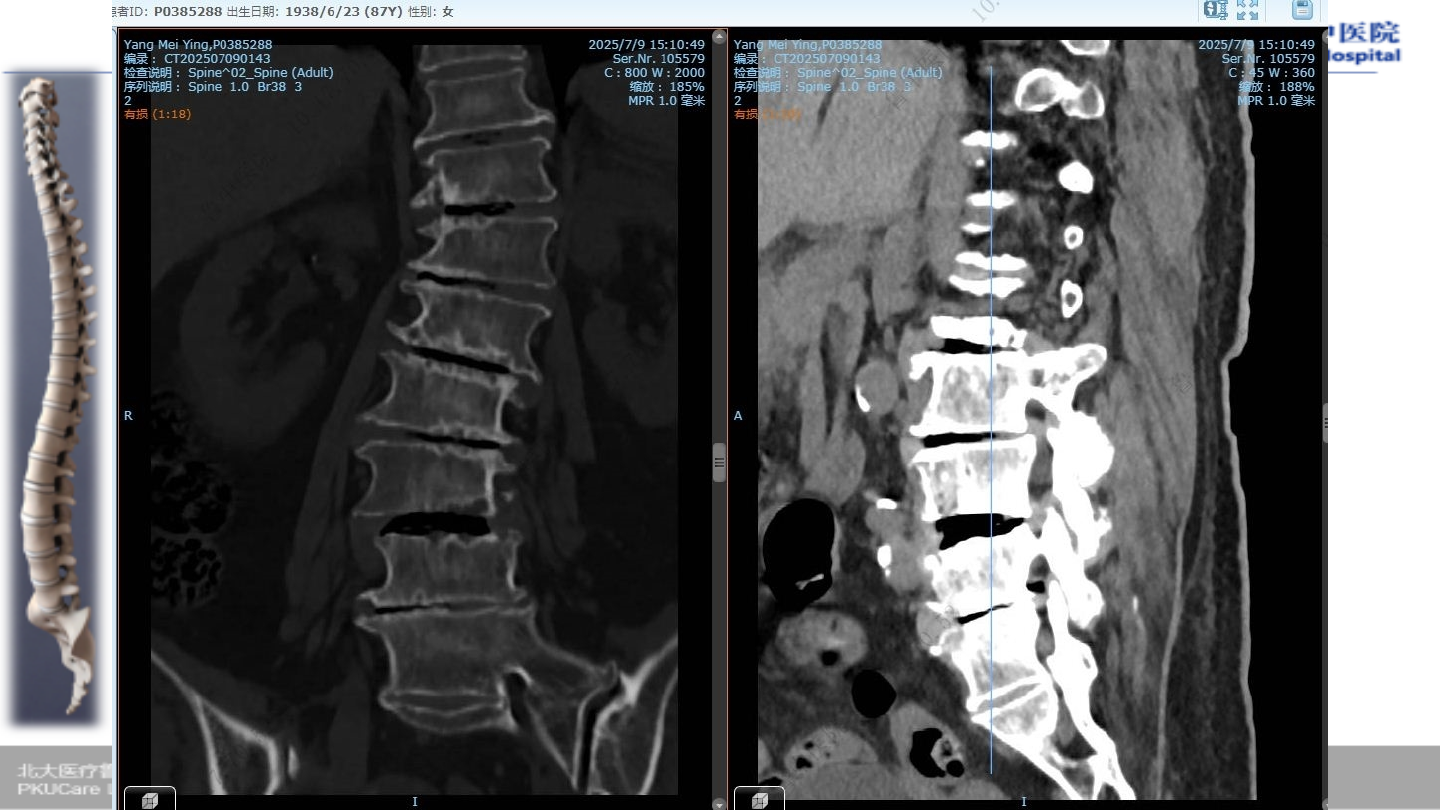

术前

CT